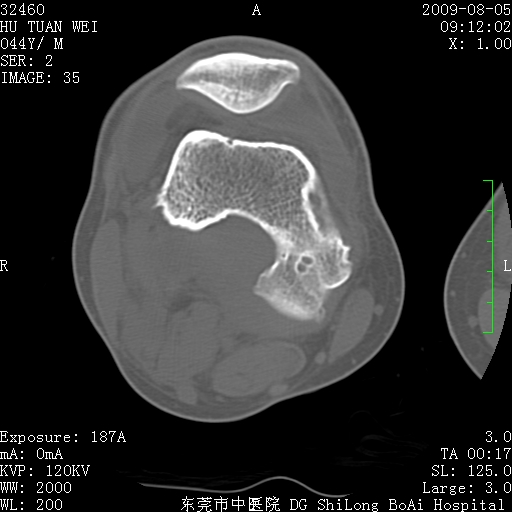

中年男性,膝韧带损伤术前检查!其他病史不清粗,不是我接手病人、且出院了!

1、股骨下段囊状膨胀性病变,边缘硬化明显,内多个残留骨棘呈多房型改变,囊腔密度较高无钙化,膝关节滑膜囊增厚,密度增高,关节腔少量积液。考虑:邻关节囊肿、退变性囊肿(软骨下囊肿)、着色性绒毛结节性滑膜炎、abc、骨巨、良性纤维组织细胞瘤等鉴。虽然年龄偏大,部位于骨端,但有外伤史,本人还是倾向于动脉瘤样骨囊肿(abc)可能性大。邻关节囊肿及软骨下囊肿次之考虑。

2、胫骨髁间棘撕脱骨折,交叉韧带损伤可能;

3、关节退行性改变。

病理结果:色素沉着绒毛结节性滑膜炎

感谢反馈病理结果!本病为慢性关节病变。以关节滑膜高度增生、绒毛结节形成伴含铁血黄素趁着为特点。病因:有炎症、肿瘤、外伤关节出血、代谢障碍、变态反应及感染等学说。增强扫描呈关节腔内单个或多个强化的软组织结节影或滑膜不规则增厚伴关节积液为本病的特征性表现。